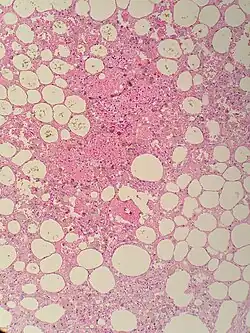

Sclerosing mesenteritis - note the hemosiderin, chronic inflammation | |

The disorder is identified by histopathology showing fat necrosis, fibrosis and chronic inflammation of the small intestine. Examination of the mesentery may indicate a solitary mass, but diffuse mesentery thickening is common.[4][6]